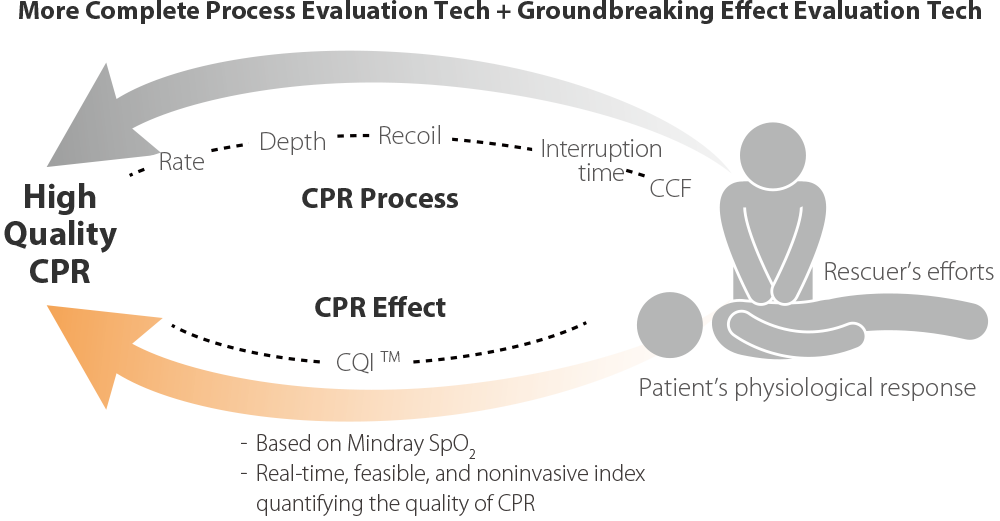

TriÃĄngulo de auxilio, mÃĄs completo

ReanimaciÃģn mÃĄs rÃĄpida